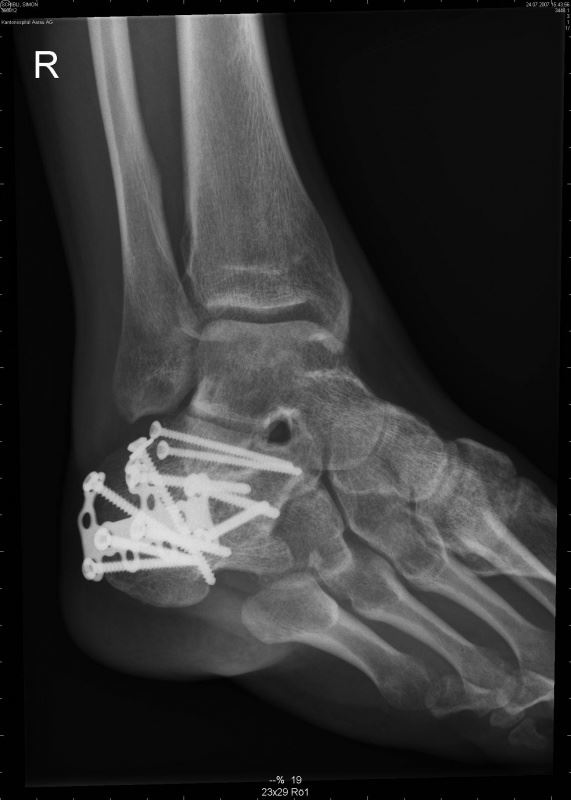

min scheiss Färsebroch